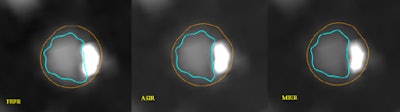

In a study that reconstructed ex vivo coronary vessel segments using three different reconstruction methods, the study team found that, indeed, accuracy in plaque quantification depended on the reconstruction algorithm, as well as vessel size and the extent of calcifications. Using advanced reconstruction, fewer corrections were needed to the vessel wall segmentation, Puchner reported at the 2013 European Congress of Radiology (ECR) in Vienna. Specifically, they compared the use of automated vessel assessment using model-based iterative reconstruction (MBIR, GE Healthcare) compared with an earlier IR algorithm, advanced statistical iterative reconstruction (ASIR, GE), or conventional filtered back projection (FBP) reconstruction.

For subjects, the group examined three ex vivo human hearts imaged with CCTA and reconstructed with FBP, ASIR, and MBIR. An automated plaque quantification tool (Vitrea Cardiac Solutions, Vital) was applied to each of the three reconstruction algorithms to fit the outer and inner vessel wall boundaries in nine "triplets" constituting 27 vessels. Only the first 40 mm of the contrast-filled vessels was used for analysis.

Each coronary cross section for which the software assigned incorrect boundaries was tallied and corrected in a blinded manner. The group then compared the number of vessel wall corrections between the different reconstruction algorithms using a Chi-square test.

The percentage of corrected cross sections was lower for MBIR (24.1%) versus ASIR (32.4%, p = 0.0003) and FBP (36.6%, p < 0.0001) -- but the differences were only marginal between ASIR and FBP, he said.

"We found that MBIR works much better than the conventional algorithms ... significantly reducing the number of corrections needed compared to FBP and ASIR, whereas the difference between the two other algorithms was not significant," Puchner said.

The use of MBIR significantly reduced the need for vessel wall boundary corrections compared with other reconstruction algorithms, particularly at the site of calcifications.